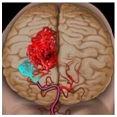

颅内动脉瘤破裂性出血 一经明确诊断,应积极行手术治疗。

动脉瘤夹闭手术具有安全高、可靠性好、手术风险可控制、治疗彻底、复发率低的优点,尤其是对于危重症患者只能行开颅夹闭术。同时费用低,普遍人群经济能力都可以承受。专家建议,颅内动脉瘤应多方咨询,对于前循环动脉瘤进行手术夹闭是一个明智的选择。